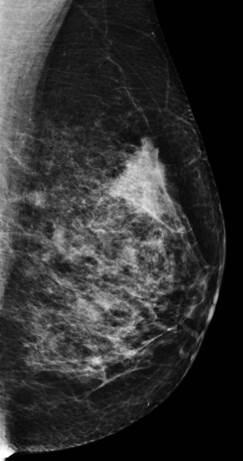

Ung thư vú

Ung thư vú - Ảnh 3

» Thông tin: Nữ giới – 58 tuổi.

» Lâm sàng: Khối tuyến vú.